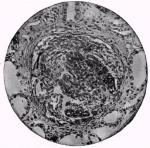

Figure 33. A glomerulus with growth Tuberculosis, syphilis, and suppurative diseases are also associated with chronic nephritis. In all probability, toxins either from a perverted metabolism or introduced from without, so influence the nutrition of the kidney as to give rise to chronic diffuse nephritis.

Figure 34. A glomerulus with the growth The large white kidney, the most common type, is usually smooth and pale, or yellowish in color, and the capsule loosely attached, so that it readily strips off. The cortex is broader than normal, owing to an extensive growth of connective tissue, and a put section reveals a yellowish-white or mottled appearance. The pyramids are highly congested and of a deep-red color. The microscope reveals the renal epithelium swollen, with fatty and granular degeneration, and the tubules of the cortex are distended with tube-casts, coagulated matter, and blood-corpuscles. Hyaline changes are also found in the epthelial cells.

The glomeruli are enlarged, the capsule cells increasing in such numbers as to compress the tufts. The interstitial tissue is increased and shows polynuclear leukocytes, red-blood cells, and round cells throughout certain areas, and some thickening of the arterial walls.